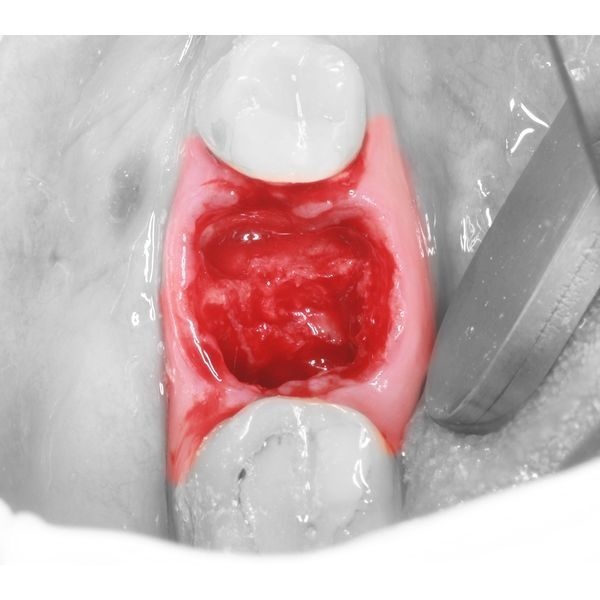

- в пустую лунку вставили модель зуба 2.8 из эпоксидной смолы, распечатанной на 3D-принтере (примерка показала, что зуб не до конца входит в лунку);

- углубили лунку с помощью твердосплавного шаровидного бора для механического наконечника, после чего модель встала на место;

- специальными щипцами удалили зуб 2.8 и установили его на место зуба 4.6, после чего зафиксировали его ортодонтической проволокой-рейтейнером и жидкотекучим композитом;